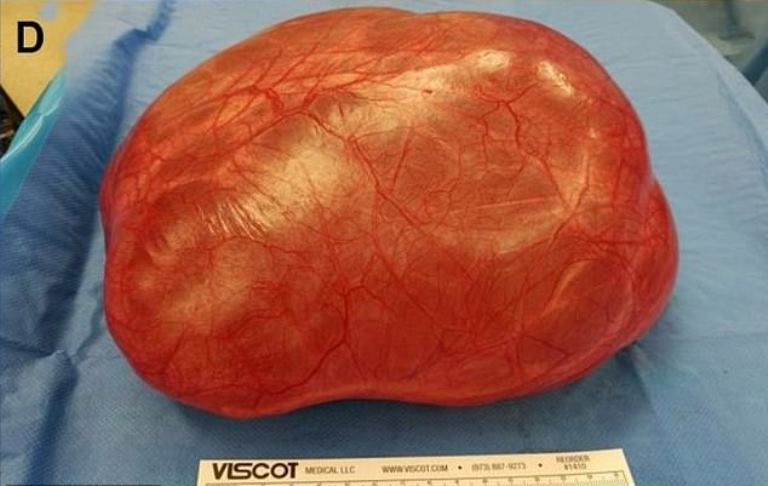

Surgeons removed the football-sized mass, which weighed 4kg (8.8lbs), and the unnamed patient recovered well.

They decided to remove the cyst in one piece instead of performing keyhole surgery, which could’ve burst the mass.

The gigantic cyst weighed 4kg and measured 21cm long. For comparison, a FA football measures 21-23 across.